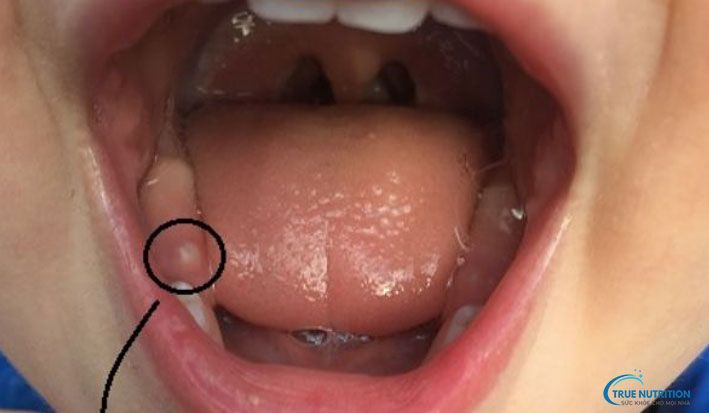

1. Hình ảnh lợi trước khi mọc răng

Trước khi răng bắt đầu nhú, lợi của trẻ thường có dấu hiệu sưng đỏ, đặc biệt ở khu vực nơi răng sẽ mọc. Vị trí này có thể xuất hiện các đốm trắng nhỏ, đó là phần đầu của mầm răng bên dưới nướu. Trẻ thường cảm thấy ngứa và khó chịu, dẫn đến việc thích cắn hoặc nhai đồ vật. Đặc điểm này rất dễ nhận biết nếu bố mẹ quan sát kỹ lợi của trẻ.

2. Hình ảnh lợi khi răng bắt đầu nhú

Khi răng sữa bắt đầu nhô lên, lợi sẽ có những vết nứt rõ rệt do răng đẩy qua lớp mô nướu. Bề mặt lợi có thể hơi rách nhẹ, lộ ra một phần chân răng màu trắng. Trong giai đoạn này, trẻ có thể đau nhức nhiều hơn, kèm theo chảy nhiều nước dãi. Đây là thời điểm quan trọng mà phụ huynh cần chú ý vệ sinh miệng cho trẻ để tránh nhiễm trùng.